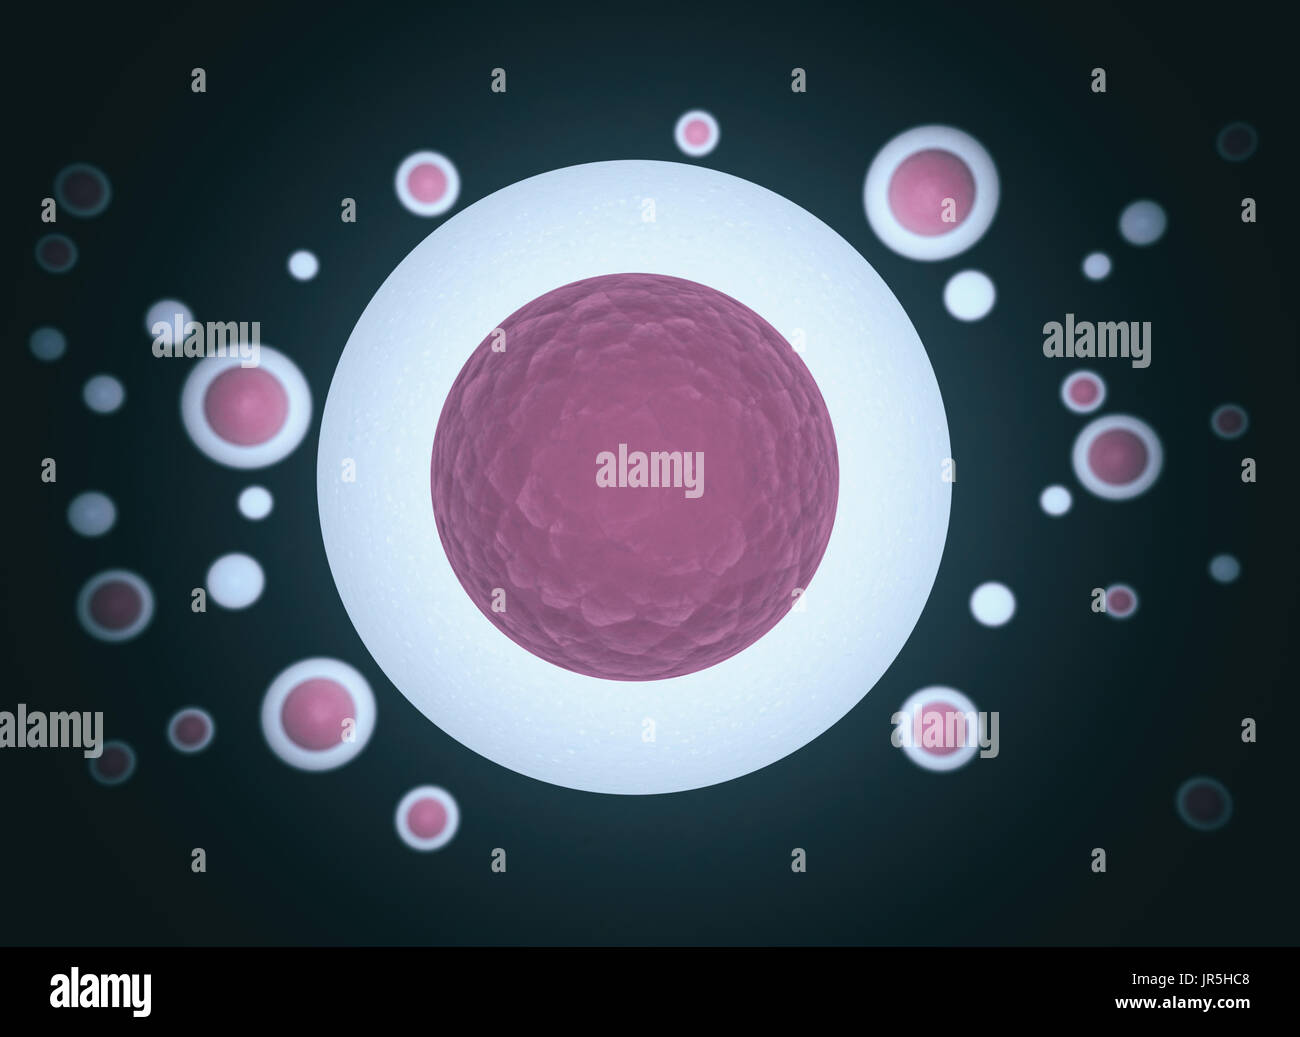

RF2YCGFJP–Rendering 3d dello sfondo del microscopio a cellule umane o cellule staminali embrionali, isolato su bianco